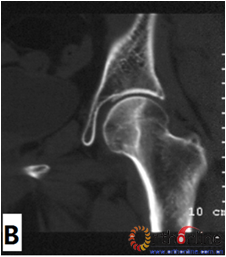

图2-2

图2 依据股骨头外侧柱存留情况,股骨头坏死的分型。(图2-1)分为Ⅰ型(外侧柱全部存留)(A)MRI图像显示;(B)7年后CT显示股骨头仍未塌陷;(图2-2)Ⅱ型(外侧柱部分保留)(A)MRI显示外侧皮质存留;(B)4年后CT显示股骨头仍未塌陷;(图2-3)Ⅲ型(坏死带穿透股骨头);(A)MRI显示坏死带;(B)2年后股骨头塌陷

Fig 2 According to preservation of the lateral pillar, the necrosis was divided into three types. (Fig 2-1)Type Ⅰ: Whole lateral pillar preserved (A) MRI showing; (B) no collapse occurred seven years later by CT showing. (Fig 2-2)Type Ⅱ: Preservation of the partial lateral pillar, (A) MRI showed the preservation of the lateral cortical bone; (B) no collapse of the femoral head four years by CT. (Fig 2-3)Type Ⅲ: the necrotic line pass through the cortical bone and bone morrow ;(A) MRI showed the necrotic line; (B) collapse of the femoral head occurred two year later.